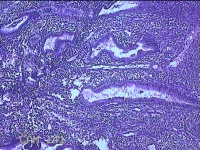

性别

女

年龄

36岁

临床诊断

右输卵管伞端妊娠流产?

一般病史

停经47天,阴道流血17天,下腹痛1天。

标本名称

宫腔内容物

大体所见

灰白暗红色不规则碎组织1.8x1.7x0.3cm一堆,未发现明显的绒毛样组织。